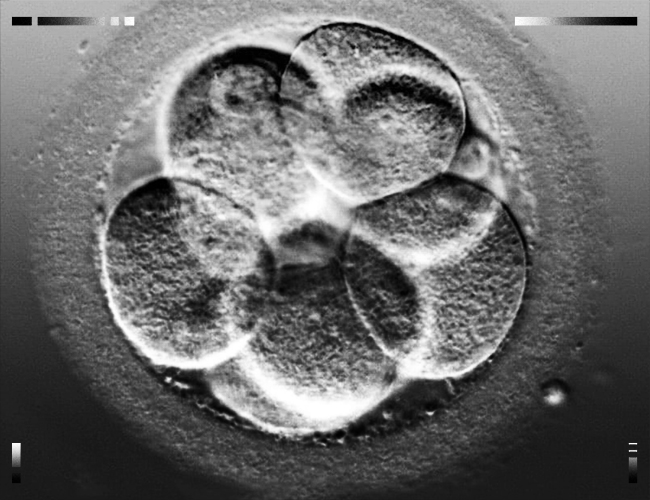

Першочергово забирають біологічний матеріал у майбутніх батьків. У жінки беруть яйцеклітину, яка штучно запліднюється спермою її партнера. Далі в лабораторних умовах вирощують ембріон, а коли він буде достатньо міцним та життєздатним — пересаджують сурогатній мамі.

Перша спроба у мене була в Києві, але провальна — ембріон не прижився. Потім виявилося, що у мене невелика фолікулярна кіста, тож на період лікування програму відклали. Проте ті ж самі батьки дали мені другий шанс. Цього разу підсаджували ембріон в Грузії — і все вийшло. Процедура відбувалася без наркозу та проходила безболісно, навіть дискомфорту не було, за що я завдячую лікарю з легкою рукою. В процесі гінекологічним дзеркалом відкривають піхву та через пробірку вводять ембріон.

Там було табло, на якому видно, як ембріон переміщується. Я на це подивилася, 15 хвилин полежала і спокійно пішла додому. З рекомендацій після цього — менше рухатися. Я після перенесення два дні старалась не ходити, в основному лежати, щоб все успішно приживалося.